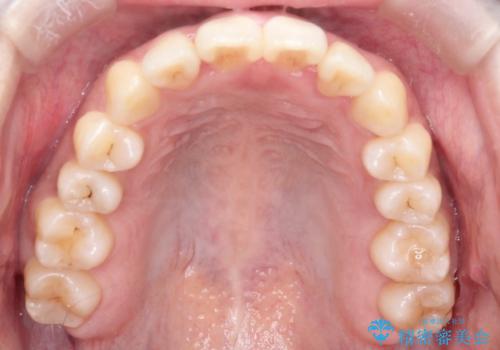

- 前歯の歯並びの改善を希望され来院された患者様です。

初診時の歯並びの状態としては、上下ともに全体に及ぶの中等度のがたつき(叢生)があり、全特に左上の前歯は1本だけ引っ込んでいる状態でした。

抜歯は行わず上顎の奥のスペースを利用して歯をスライドする方法の他に歯列弓の拡大やディスキング(歯と歯の間の隙間を作る処置)を行い叢生を改善しました。

歯の大きさの不揃いが原因の正中のズレは、ディスキング量を調整することで合わせました。

見た目、嚙み合わせ及び、治療期間や施術内容に大変ご満足いただきました。